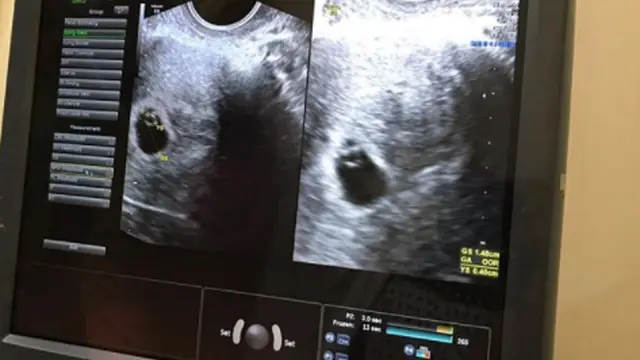

Fimela.com, Jakarta Setiap ibu hamil pasti akan melakukan USG, atau Ultrasonography untuk mengetahui usia janin, memeriksa kondisi dan kesehatan janin, serta melihat perkembangannya di dalam rahim.

USG Tetap Aman Buat Janin

Tenang, USG itu nggak bahaya buat bayi. USG membantu dokter kandungan memonitor perkembangan bayi dan juga mendeteksi apakah ada perubahan atau perkembangan yang nggak normal. Juga untuk memeriksa kapan kira-kira kamu akan ahiran.

Posisi plasenta juga bisa terlihat dari USG ini. Jadi kamu bisa tahu, apakah leher bayi terlilit plasenta atau berada di posisi normal.

Dilansir dari Parents, USG ini aman buat ibu dan janin. Karena dokter yang sudah berpengalaman akan membacakan interpretasi dari hasil USG. Selain itu, USG ini nggak seperti Sinar-X. Jadi, USG nggak akan menimbulkan radiasi.